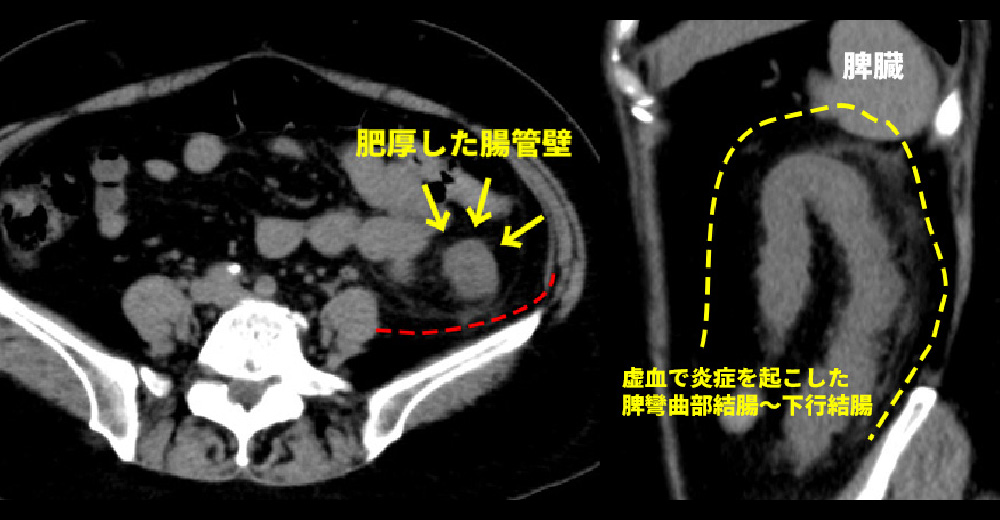

虚血性腸炎

糖尿病や高血圧、喫煙などによる動脈効果の結果、大腸粘膜の血流が減少して、粘膜の炎症が起こり、腹痛や下血を契機に診断されます。下行結腸やS状結腸に好発し、内視鏡では、腸管の縦方向にびらんや潰瘍ができます。

虚血性腸炎 虚血性腸炎